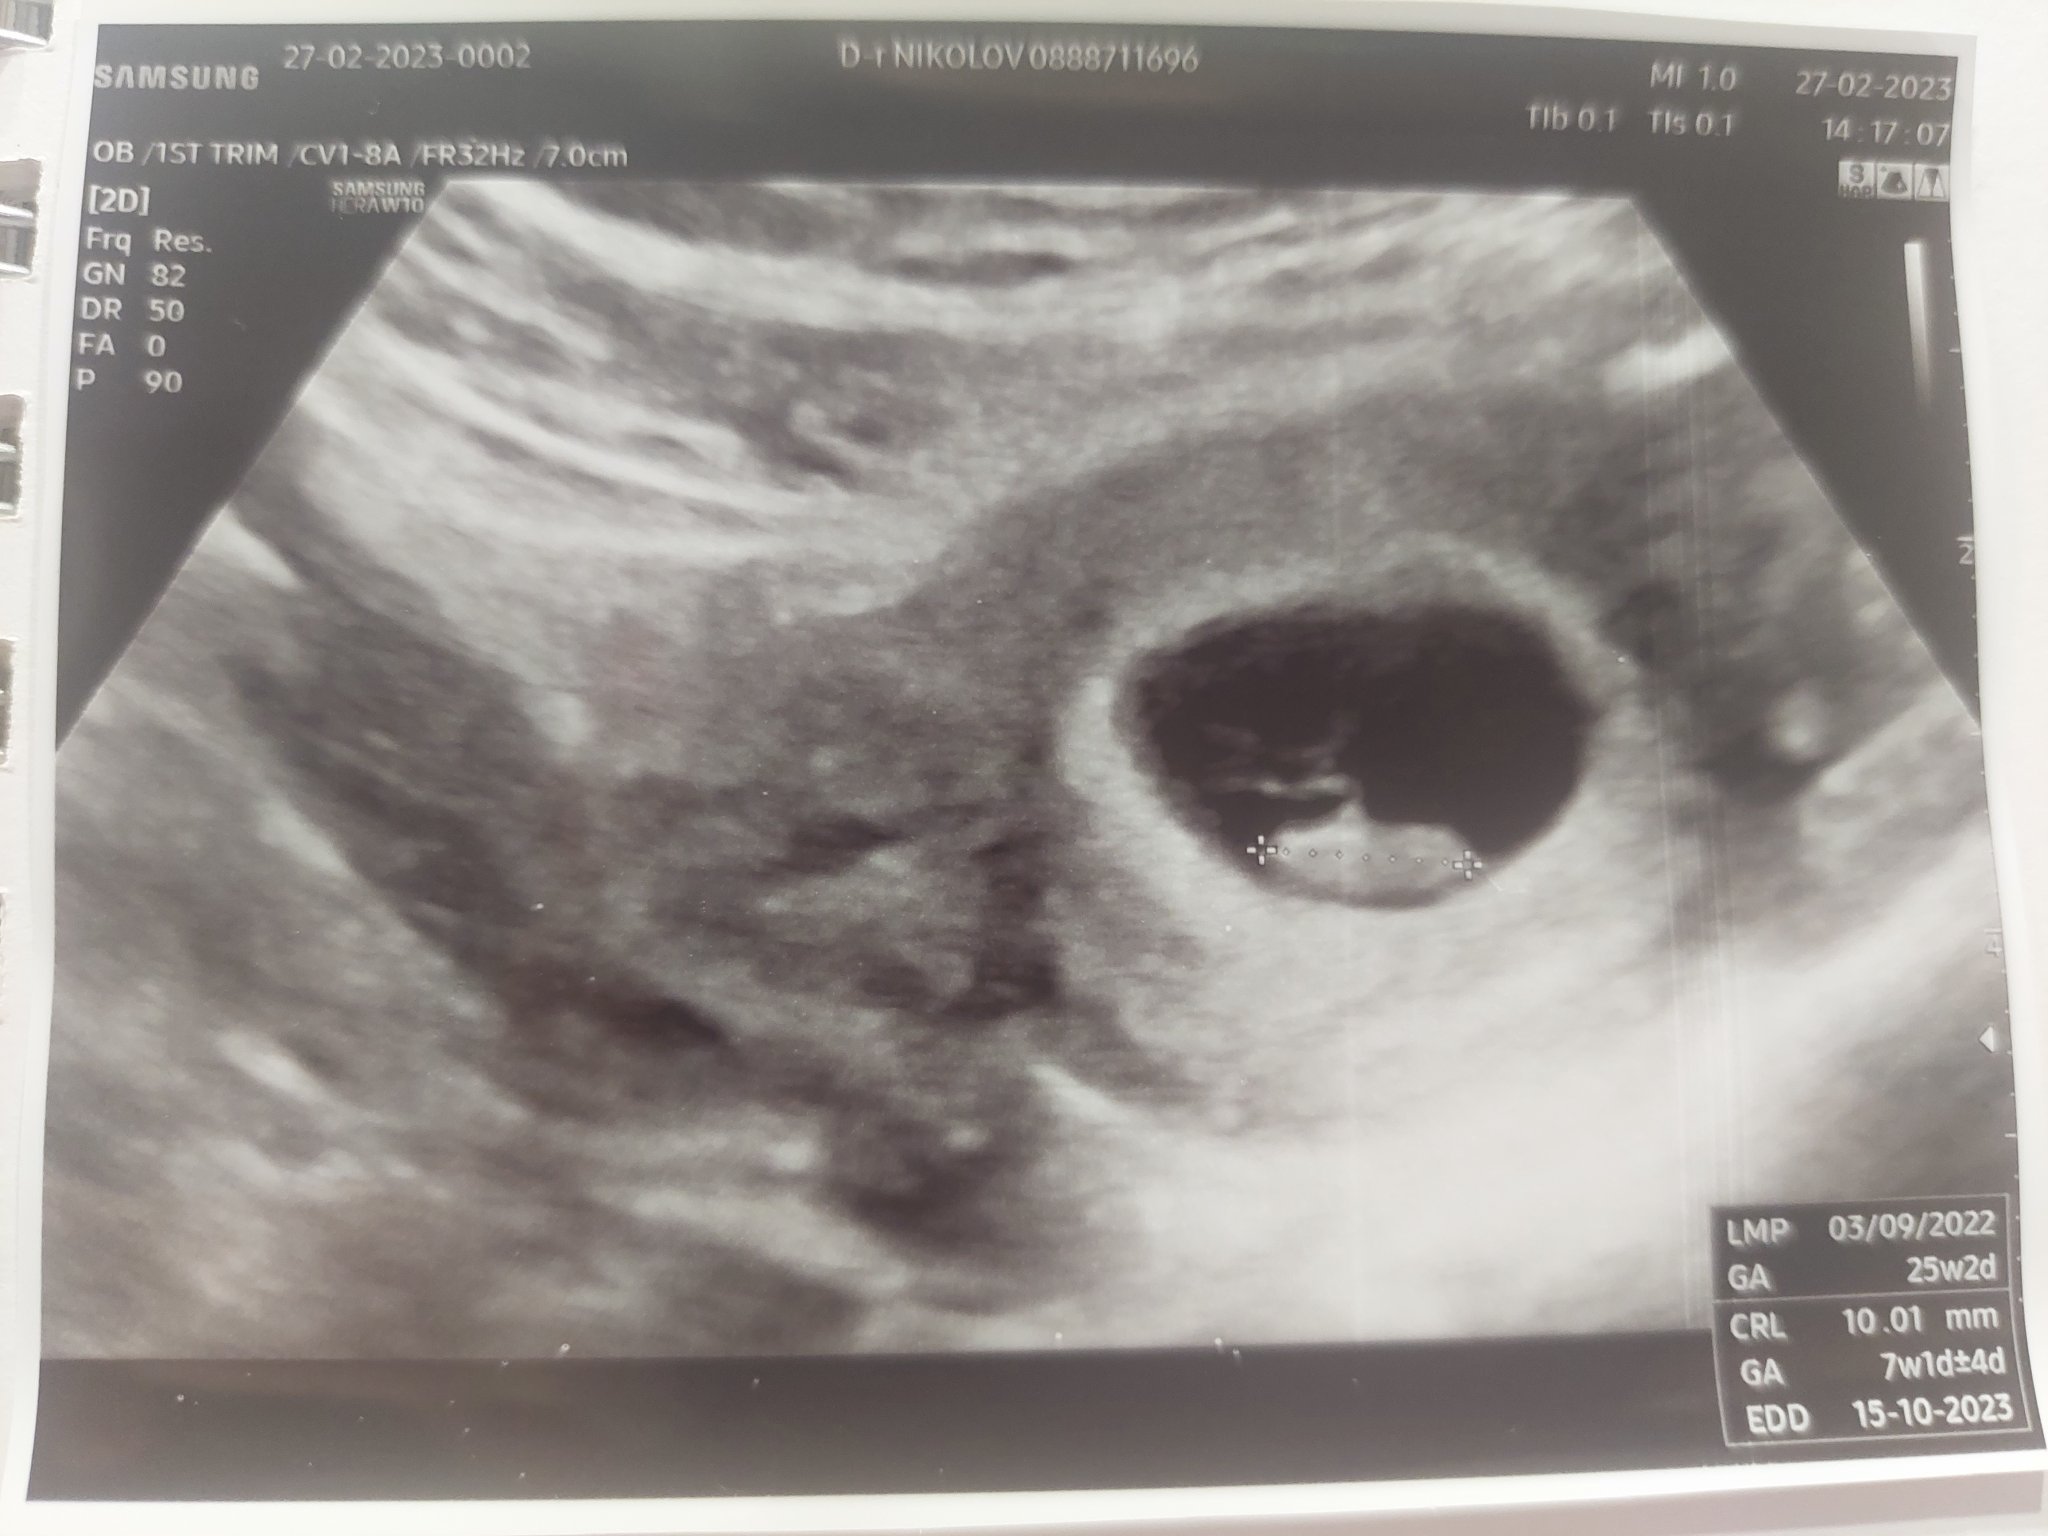

Какво представлява изображението от ехографията на 5-седмична и 2-дневна бременност?

Кога обикновено може да се види ембрионът на ултразвукова снимка?

Какво представлява жълтото тяло на ехографската снимка?